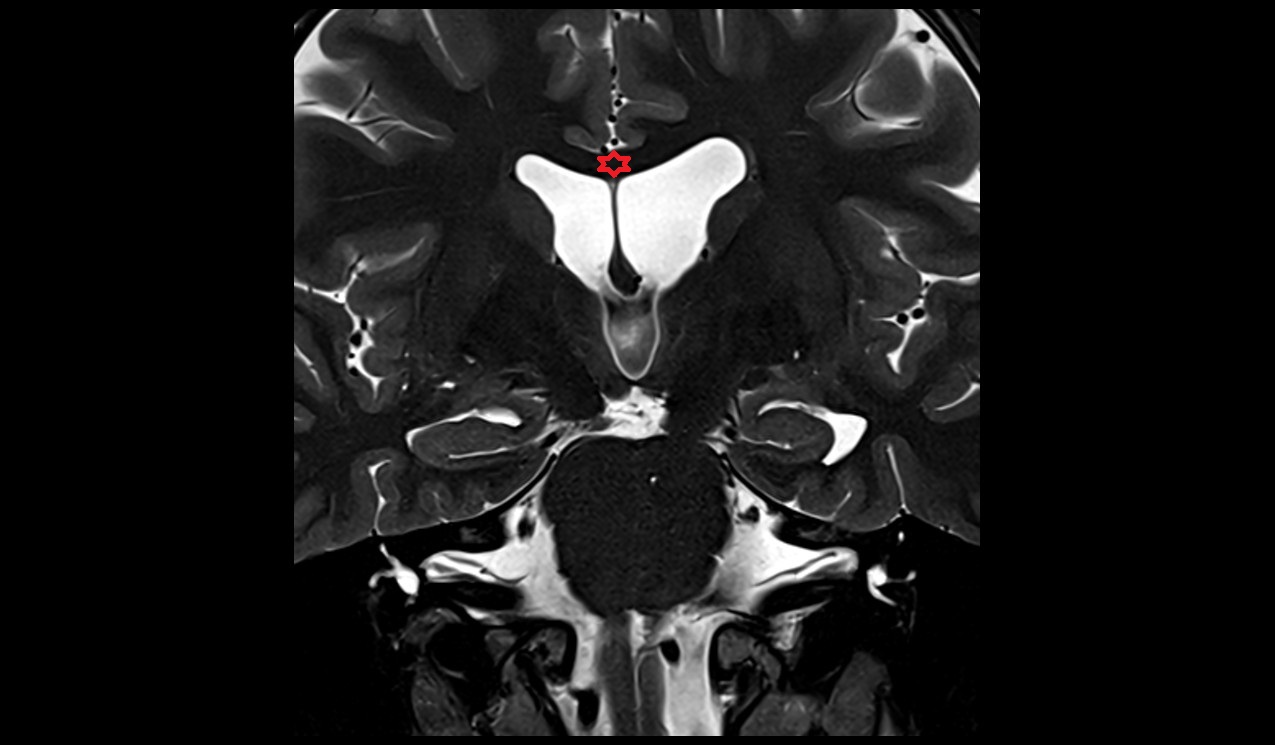

- Interventricular foramen

- Third ventricle